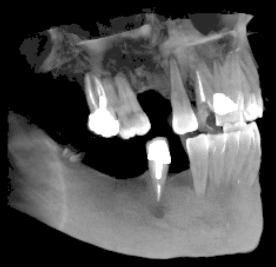

3D скенер на зъби – две челюсти

Тризмерният CBCT образ на двете челюсти дава възможност за диагностициране на състоянието на цялото съзъбие. Приложението е аналогично на 3D скенера на една челюст.